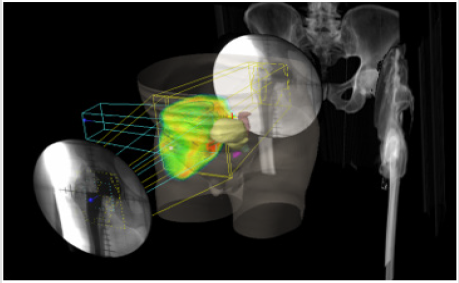

Male patient with 67 years of age, with previous total hip replacement 7 months ago. His comorbidities were osteoporosis, heart valve replacement and diabetes induced kidney injury. One month after surgery his radiograph showed smoldering signs of HO (Brooker I/II – Figure 4). Patient gradually developed pain, which got worse with time and decrease joint motion with progressively inability to flexion and elevation of the leg. On the control radiograph taken 5 months after surgery there were signs of HO Brooker III (Figure 5) and patient became more symptomatic with pain level 10 out a scale of 10. He presented to our department on February 2019 with functional impairment, depression, pain and inability to perform his daily activities like driving. We performed a CT simulation on supine positioning, followed by a 3D conformal RT planning and treatment was delivered with a single fraction of 800 cGy on linear accelerator using photon energy of 18MV covering the entire joint (Figure 6). On the follow-up visit, one month after treatment, patient showed a decrease on his pain level (from 10 it decrease to 5 out a scale of 10) and regain some level of joint motion that allowed him to drive again and do some of his life activities.

Kantor, also achieved no further HO progression after EBRT treatment in patients with significant HO diagnosed more than 6 weeks after surgery [22]. Based on this postulated, we report a case of a patient treated only with single fraction of 800 cGy for a Brooker III hip HO, 6 months after surgery and he had a significant improvement of his pain and mobility, which ultimately led to an improved quality of life. Similarly, Tao et al. reported a case of a patient with extensive HO treated with a single fraction of 800 cGy and, at the 6-month follow-up visit, the patient also reported significant palliation of symptoms without signs of HO progression on radiographic images [14]. In terms of EBRT technique it seems that CT based EBRT allows more accurate delineation of the tissues and better clinical outcomes according to Mourad et al. [23]. In this article we reported two cases, one of them received 2D treatment and the other 3D conformational treatment. Both of them achieved relief of their symptoms and none experienced any immediate complications. However CT based EBRT is associated with additional cost which should be taken in consideration when treating these conditions.